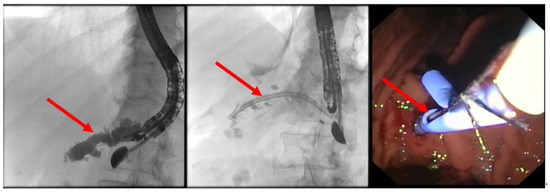

(A) EUS-ERP rendezvous technique: If the wire can be passed through the papilla and the papilla is accessible with the endoscope, a duodenoscope is employed. The guidewire is then grasped with forceps and pulled out, enabling subsequent conventional ERP with endoscopic papillary balloon dilation (EPBD) and stent placement (Figure 3 and Figure 4).

Figure 3. EUS puncture with a 19-G needle tangentially toward the papilla; the wire is passed out of the papilla via a ring knife, followed by device change of the duodenoscope.

Figure 4. After the device change, the wire is grasped with forceps and passed out, followed by a conventional ERP with stent placement (red arrow).